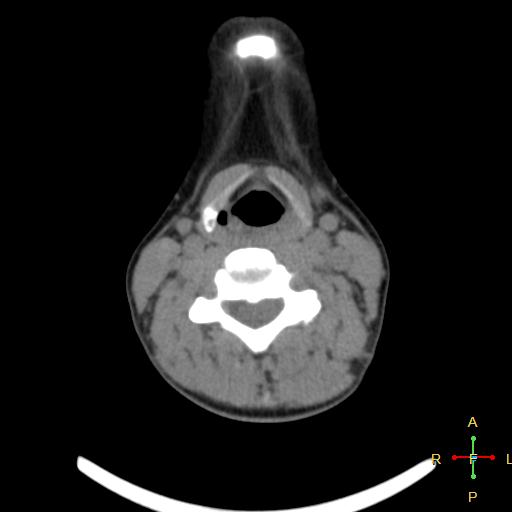

Уважаемые коллеги, помогите пожалуйста. Проводилось обследование МСКТ гортани, пациентка 40 лет, жалобы на осиплость голоса в течение последней недели, при физикальном осмотре ЛОР врачом - голосовые...

Добрый вечер! Помогите, пожалуйста,разобраться в МСКТ. Женщина, 55 лет. 27 января 2014г прооперировали по поводу ПРЩЖ с mts в лимфоузлы шеи , тиреоидэктомия с центральной лимфодиссекцией и футлярно-...